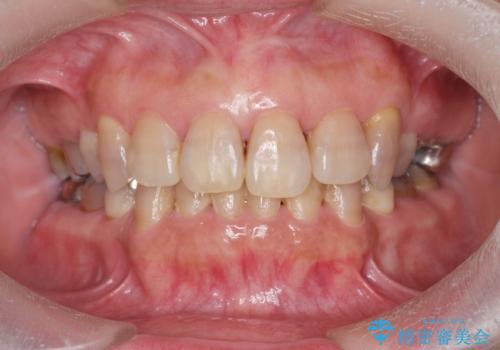

[メタルフリー] 虫歯・銀歯だらけの口腔内を全顎治療

![[メタルフリー] 虫歯・銀歯だらけの口腔内を全顎治療の症例 治療前](https://seimitsushinbi.jp/wp/wp-content/uploads/2025/03/e26a9887bc6905a2f0f51f5772b5ac9c-500x350.jpg?v=1741918285)